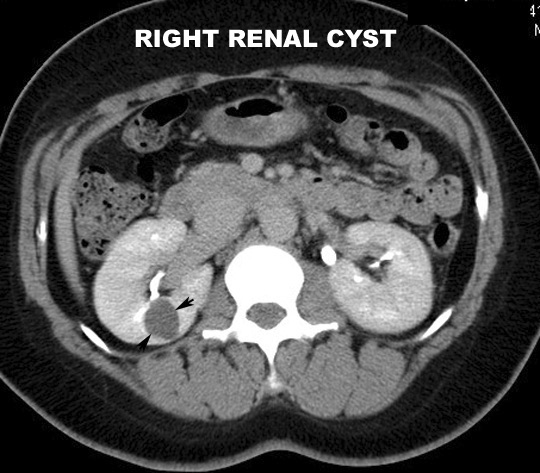

Contrast CT characteristics: